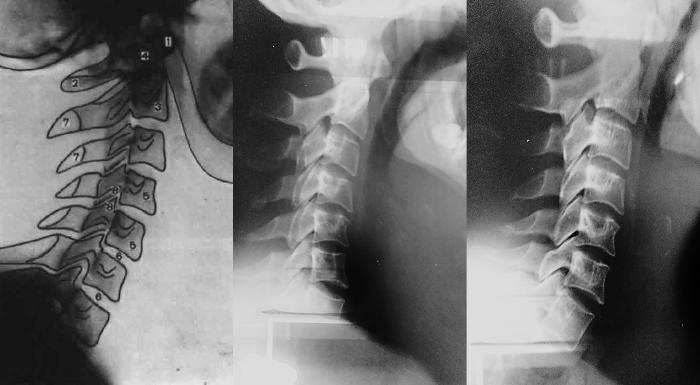

Тем не менее полученная в родах травма не всегда видна с детства и сказывается на пациенте только в зрелости. Вот пример. Ниже на рентгене можно увидеть нормальный изгиб шейного отдела позвоночника – слегка вперёд.

А вот – на снимке по середине – шея пациента со смещением первого шейного позвонка. Очевидно, что в шее не просто отсутствует лёгкий прогиб вперёд, она слегка выгнута назад, то есть в таком состояние она не приспособлена к правильному распределению нагрузки. У пациента был поставлен диагноз «остеохондроз шейного отдела».

Справа показан рентген того же пациента через несколько месяцев после проведения атластерапии – шея начинает приобретать правильный изгиб. Она восстанавливается.